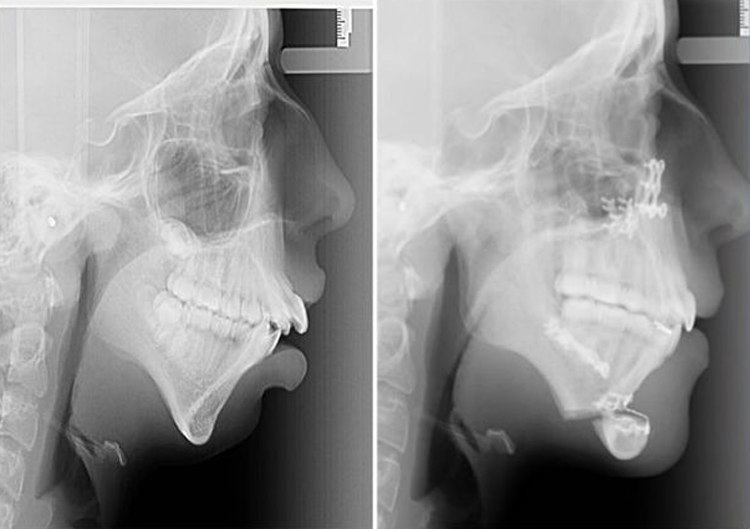

ऐली जोंस – X-Rays मे पहले और बाद मे :

लेकिन ऐली के लिए ये सर्जरी इतनी आसान नही थी। उसे एक महीने एक तरल भोजन के ऊपर निर्भर रहना पडा। फिर भी ऐली इसके लिए तैयार थी क्योकि उसकी ज़िंदगी बदलने वाली थी। 6 माह के बाद उसने prom party को attend किया। और अब वह पहले से अधिक खुश है।

एक साल बाद, वह फिर से अपने चेहरे मे अंतिम बदलाव के लिए सर्जरी की दूसरी स्टेज के लिए तैयार थी। इस बार उसके corrective surgery के द्वारा उसके ठुड्डी की आकृति को ठीक किया गया।